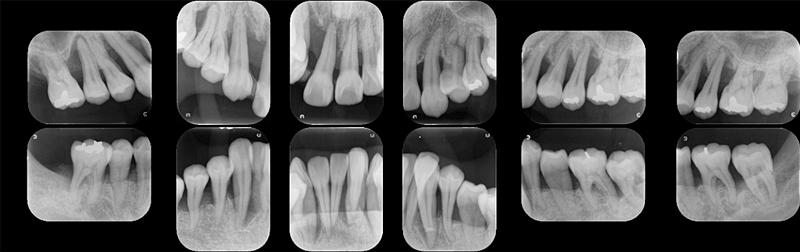

下の14枚法専門的エックス線診査は来院された40歳前半の女性の方で他の医院でほとんどの歯が抜歯といわれたそうです。侵襲性歯周炎の患者さんの特徴である著しい骨の吸収(骨が溶ける)が認められます。抗菌療法と完全な感染除去の基本治療が終了し、外科治療、そのあと矯正治療に入る予定です。